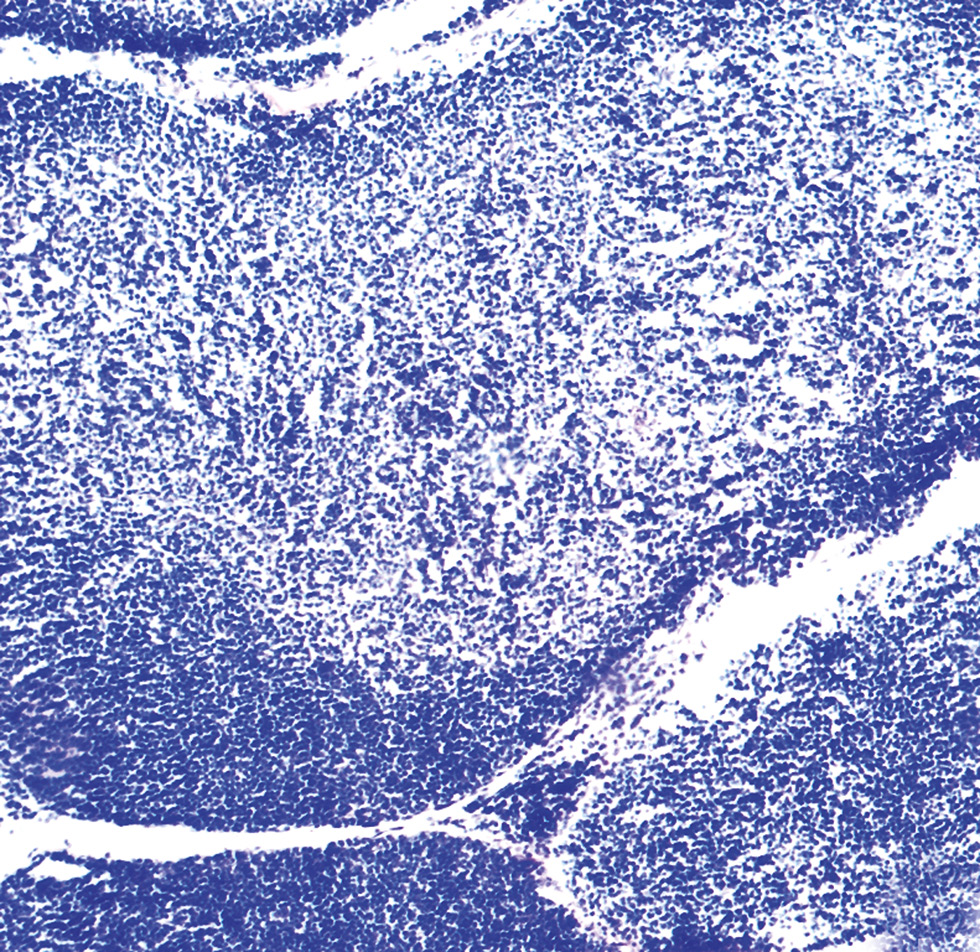

Данные гистологического исследования представлены на рис. 1. В полости заплюсневого сустава выявлены отёчная жидкость, выраженный отёк тканевых структур суставной сумки и полнокровие синовиальной оболочки с полиморфно-клеточной инфильтрацией, с преобладанием лимфоцитов и множественными васкулитами (рис. 1, a).

Необходимо отметить, что при клебсиеллёзно-кандидозном артрите наблюдается выраженная дезорганизация соединительнотканных структур суставной сумки. Синовиальная оболочка резко утолщена, отёчна, гиперемирована. Ворсины её подвергнуты гиперплазии, покрыты фибринозным экссудатом, пропитаны нейтрофильными гранулоцитами, лимфоцитами и макрофагами. Дистрофические изменения в стенках сосудов проявляются развитием васкулита, панартериита и периартериита в синовиальной оболочке.

Модель клебсиеллёзно-кандидозного артрита отличается выраженным разрушением суставных хрящей с формированием очагов некроза на суставной поверхности и резорбцией субхондральной костной ткани. При этом отмечаются узуры (эрозии), фиброзные спайки, аномальные очаги хондро- и остеогенеза. Воспроизведённая модель характеризуется также развитием мелкоочаговых гнойно-некротических процессов в гиподерме и дерме околосуставной области, с наличием микроабсцессов и остеомиелита в костных структурах диафиза (рис. 1, b). Описанные выше изменения свидетельствуют о формировании на суставной поверхности грануляционной ткани в виде паннуса, приводящего к фиброзному анкилозу сустава (рис. 1, c).

Рис. 1. Гистологические изменения в тканях поражённых суставов крыс с модельным артритом (срез заплюсневого сустава; окраска — гематоксилин Майера и эозин; окуляр — ×10 , объектив — ×20): a — полиморфно-клеточная инфильтрация суставной сумки; b — признаки остеомиелита в костных структурах диафиза; c — формирование паннуса за счет инфильтрации синовиальной оболочки клетками грануляционной ткани. Масштабный отрезок — 20 мкм.